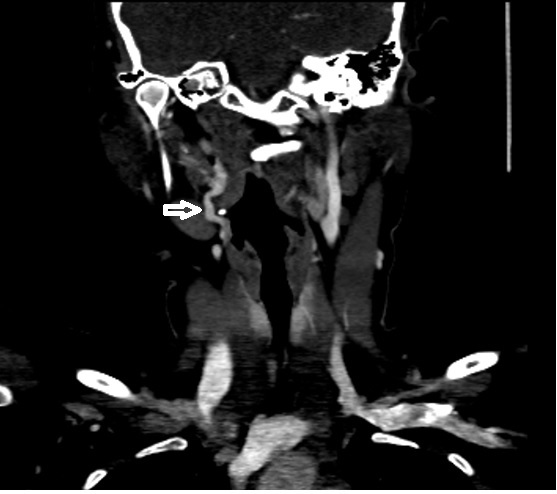

Pulsatile tinnitus (PT) manifests as an auditory sensation synchronised with the heartbeat, occurring without any external auditory stimuli. While its etiology is diverse, vascular factors predominate. We present two intriguing cases of unilateral PT with unremarkable otorhinolaryngological examinations: one attributed to tortuosity of the extracranial internal carotid artery (ICA) and the other to dehiscence of the sigmoid sinus wall. Both patients exhibited a common characteristic whereby compression of the ipsilateral jugulo-carotid region relieved their tinnitus. Diagnostic imaging, including High Resolution Computed Tomography (HRCT) of the temporal bone and Computed Tomography Angiography (CTA) of the head and neck, facilitated accurate diagnosis in both instances. The majority of PT cases have identifiable causes, with imaging modalities playing a pivotal role in diagnosis. Treatment options range from observation with reassurance to medical intervention or surgical management.

CTA showing tortuosity of right extracranial ICA at level C2 (white arrow)